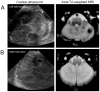

Objective: To investigate the relationship between cerebellar hemorrhage in preterm infants seen on magnetic resonance imaging (MRI), but not on ultrasonography, and neurodevelopmental outcome.

Results: Cerebellar hemorrhage was detected on both ultrasonography and MRI in 3 of the 131 preterm newborns evaluated, whereas smaller hemorrhages were seen only on MRI in 10 newborns (total incidence, 10%). Adjusting for gestational age at birth, intraventricular hemorrhage, and white matter injury, cerebellar hemorrhage detectable solely by MRI was associated with a 5-fold increased odds of abnormal neurologic examination compared with newborns without cerebellar hemorrhage (outcome data in 74%). No association with the Wechsler Preschool and Primary Scale of Intelligence, Third Edition score was found.

Conclusions: Cerebellar hemorrhage is not uncommon in preterm newborns. Although associated with neurologic abnormalities, hemorrhage seen only on MRI is associated with much more optimistic outcomes than that visible on ultrasonography.